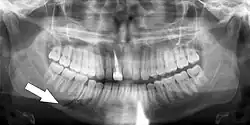

Panoramic radiograph showing horizontally impacted lower wisdom teeth.